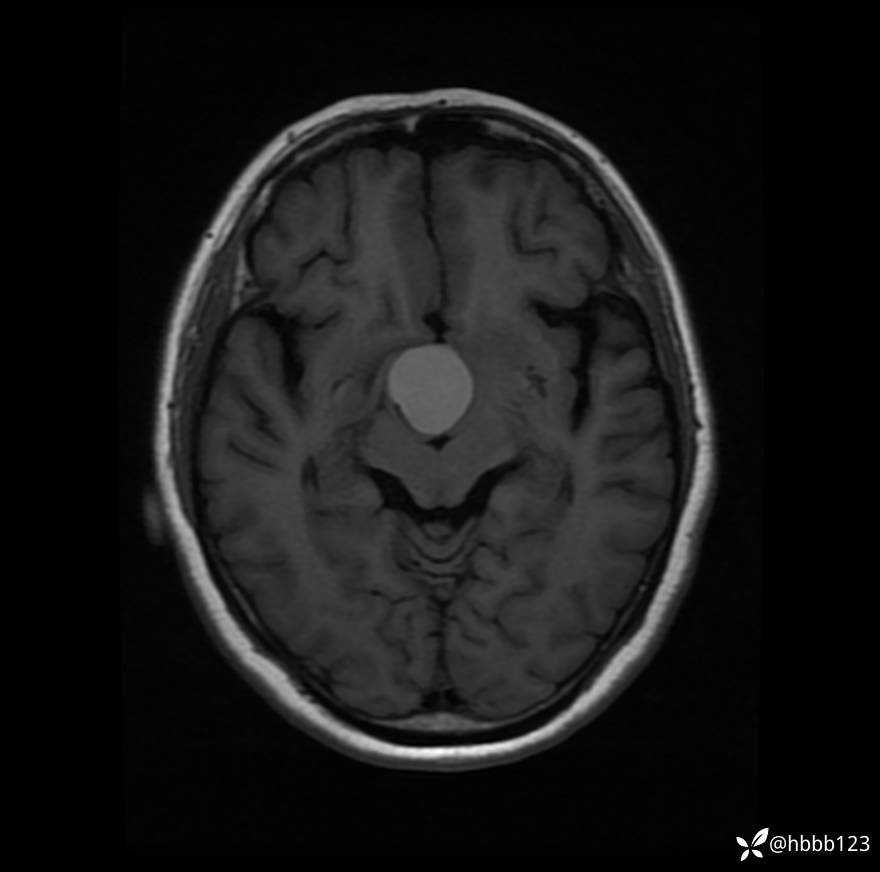

T1WI: